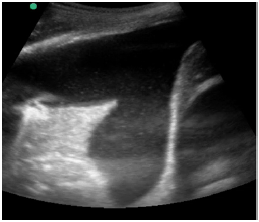

Um paciente de 50 anos de idade encontra-se, internado na UTI por conta de choque séptico de foco pulmonar, em ventilação mecânica na modalidade pressão e no modo assisto-controlado. Pela manhã foi submetido a acesso venoso central em veia axilar guiado por ultrassonografia. Ao exame físico, notou-se que o paciente está com hipotensão e taquicardia. A primeira hipótese diagnóstica é pneumotórax e é realizada radiografia com imagem apresentada.

Qual imagem abaixo corresponde ao achado ultrassonográfico para o paciente em questão?